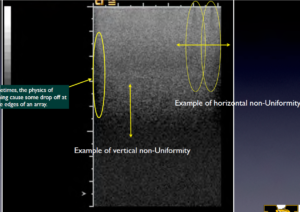

With basic B-mode imaging (shown below) two parameters of performance can be qualitatively assessed using a TMP; sensitivity (the ability to discern faint echoes) and uniformity (homogeneity of the echoes, see photo below, left). In addition to be a qualitative test this is also a subjective test as it relies on the visual acuity of the tester to detect small variances in the image. Using a TMP also is complicated by the desire (sometimes subconsciously) to make an image captured during today’s test “look” like the one that was captured during a previous test, usually by adjusting the TGC controls, gain, and various processing functions. Modern systems also have heavily averaged image processing algorithms such as Spatial Compounding that can mask transducer problems such as dead elements, as demonstrated in the image below, right. Lastly, because of the rather narrow range of gray scale visual acuity in humans the TMP test results can be misinterpreted by someone who may not be able to discern subtle differences in the image.